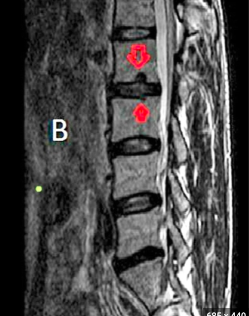

Q

What are the arrrows pointing to? [1]

A

Schmorl’s nodes